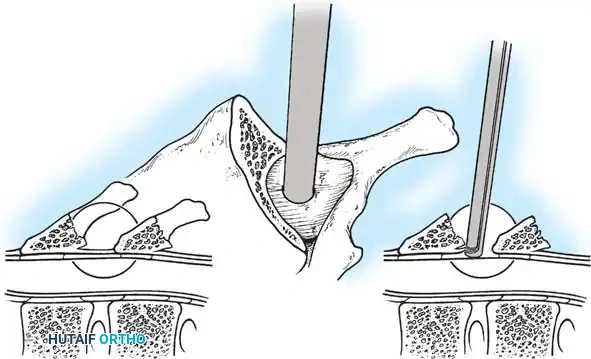

The Hall Technique

The Hall technique offers an alternative method for facet obliteration and grafting, particularly useful in rigid deformities.

Fig. 38-28: The Hall technique of facet fusion, involving sharp excision of the inferior facet and trough creation.

- Sharply amputate the inferior articular facet with a gouge and remove the bone fragment entirely. This exposes the cartilage of the superior facet.

- Remove the exposed cartilage completely with a sharp curet.

- Create a bleeding trough by removing the outer cortex of the superior facet.

- Impact cancellous bone grafts directly into this vascularized trough.

- Complete the procedure with global decortication of the posterior elements.